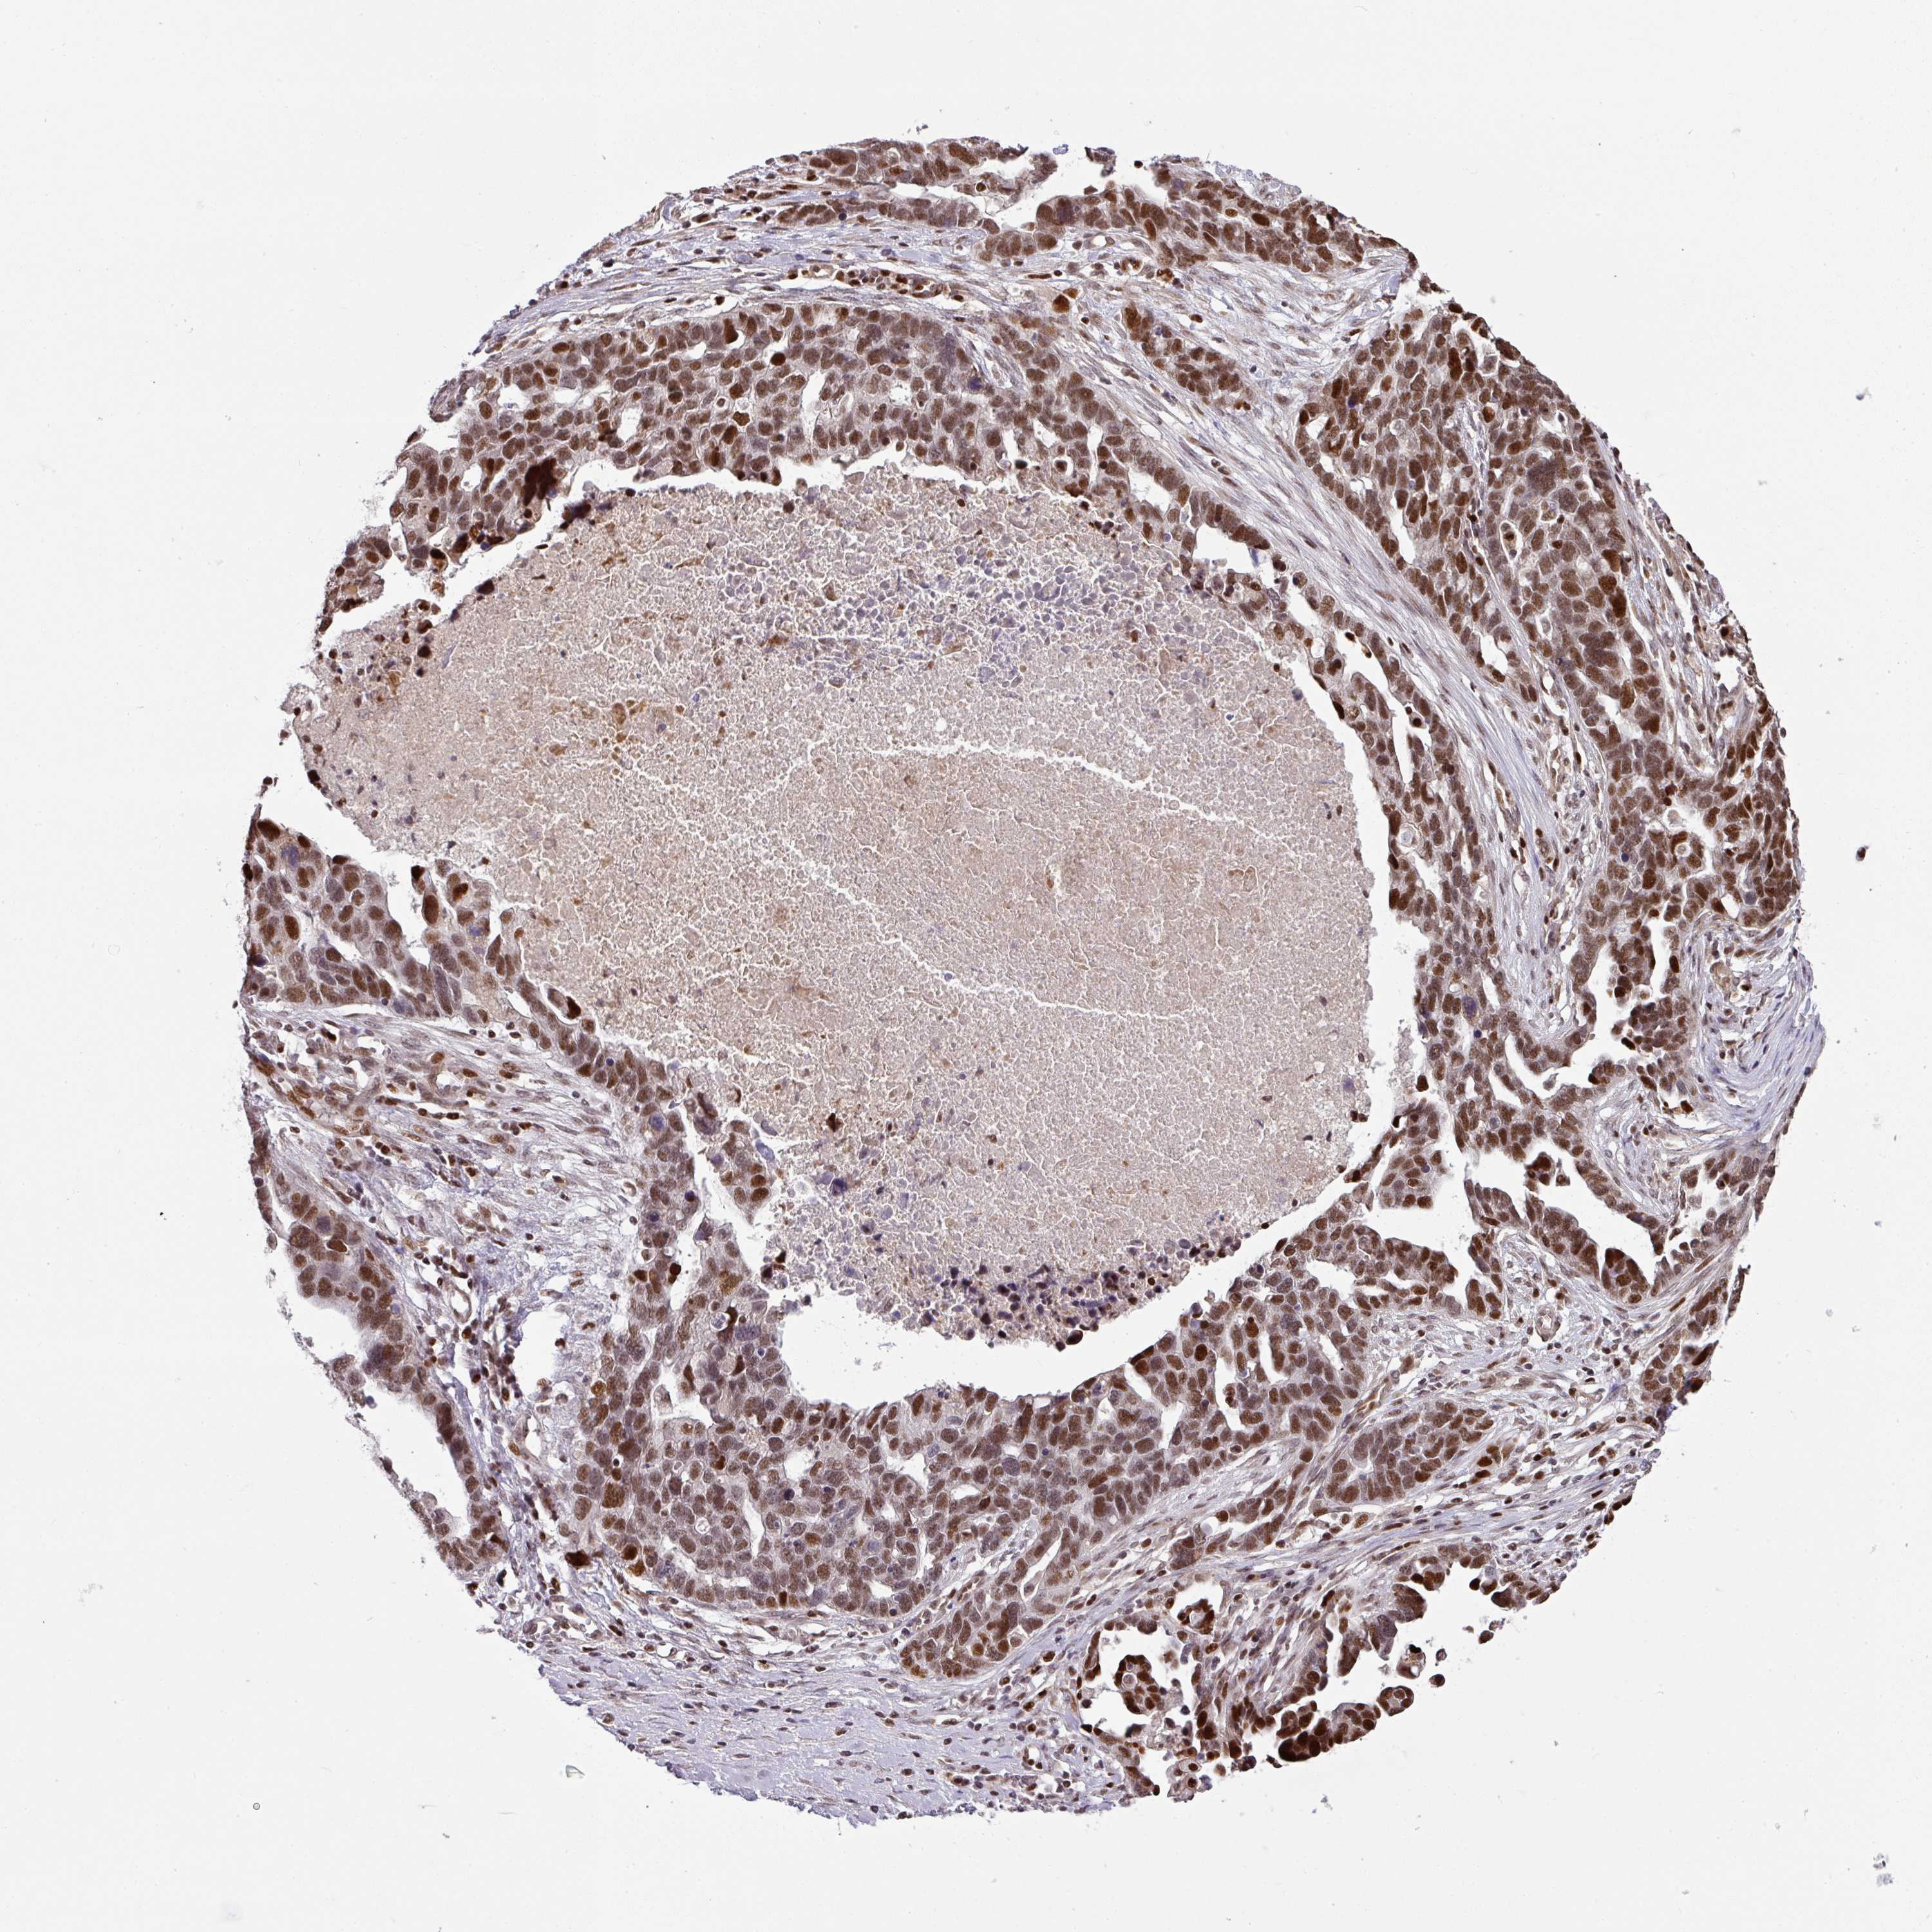

OVARIAN CANCER - Protein expressioni

A mouse-over function shows sample information and annotation data. Click on an image to view it in a full screen mode. Samples can be filtered based on level of antibody staining by selecting one or several of the following categories: high, medium, low and not detected. The assay and annotation is described here.

Note that samples used for immunohistochemistry by the Human Protein Atlas do not correspond to samples in the TCGA dataset.

Antibody stainingi

Antibody staining in the annotated cell types in the current human tissue is reported as not detected, low, medium, or high, based on conventional immunohistochemistry profiling in selected tissues. This score is based on the combination of the staining intensity and fraction of stained cells.

Each image is clickable and will lead to virtual microscopy that enables deeper exploration of all samples and also displays staining intensity scores, fraction scores and subcellular localization as well as patient and tissue information for each sample.

Antibody HPA054291

Staining

High

Medium

Low

Not detected

Intensity

Strong

Moderate

Weak

Negative

Quantity

>75%

75%-25%

<25%

None

Location

Nuclear

Cytoplasmic/membranous

Cytoplasmic/membranous,nuclear

Cystadenocarcinoma, serous, NOS

Carcinoma, NOS

Cystadenocarcinoma, mucinous, NOS

Carcinoma, endometroid